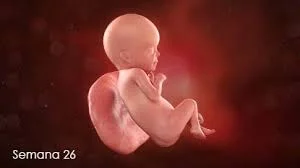

• Semana 26

Semana 26

El feto mide aproximadamente 24 cm y pesa cerca de 800 gramos. Los ojos se abren por primera vez, y el feto puede responder a la luz que atraviesa el abdomen de la madre. Los patrones cerebrales son más complejos, y los movimientos fetales se vuelven más organizados. El sistema inmunológico comienza a desarrollarse más completamente.